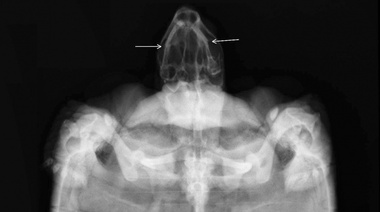

Terapia complementaria en ejemplar de Chelonoidis chilensis para la recuperación post fractura de mandíbula

03/01 | Se describe el caso clínico de una tortuga macho que concurrió a consulta de urgencia luego de haber sido mordida por un canino. El paciente se presenta con herida perforante en la cabeza que le provocó abundante sangrado y fractura de mandíbula. La recuperación del paciente se complementó con fisioterapia.

Urgencias en tortugas de tierra: la hora dorada en el paciente quelonio

22/07 | Artículo destacado de la edición Nº 129 de la revista Vet Market. Los autores son los Dres. Camila Lascano y Vedia, Nicolás Cohen y Fernando Pedrosa, integrantes de Fauna Vets.